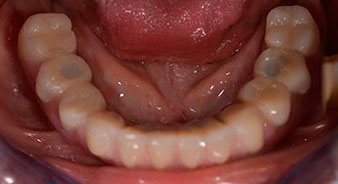

Пациентката е 64-годишна жена с частично обеззъбяване на зъби 38, 33 и 43 и частична долночелюстна протеза (Фиг. 1 и 2).